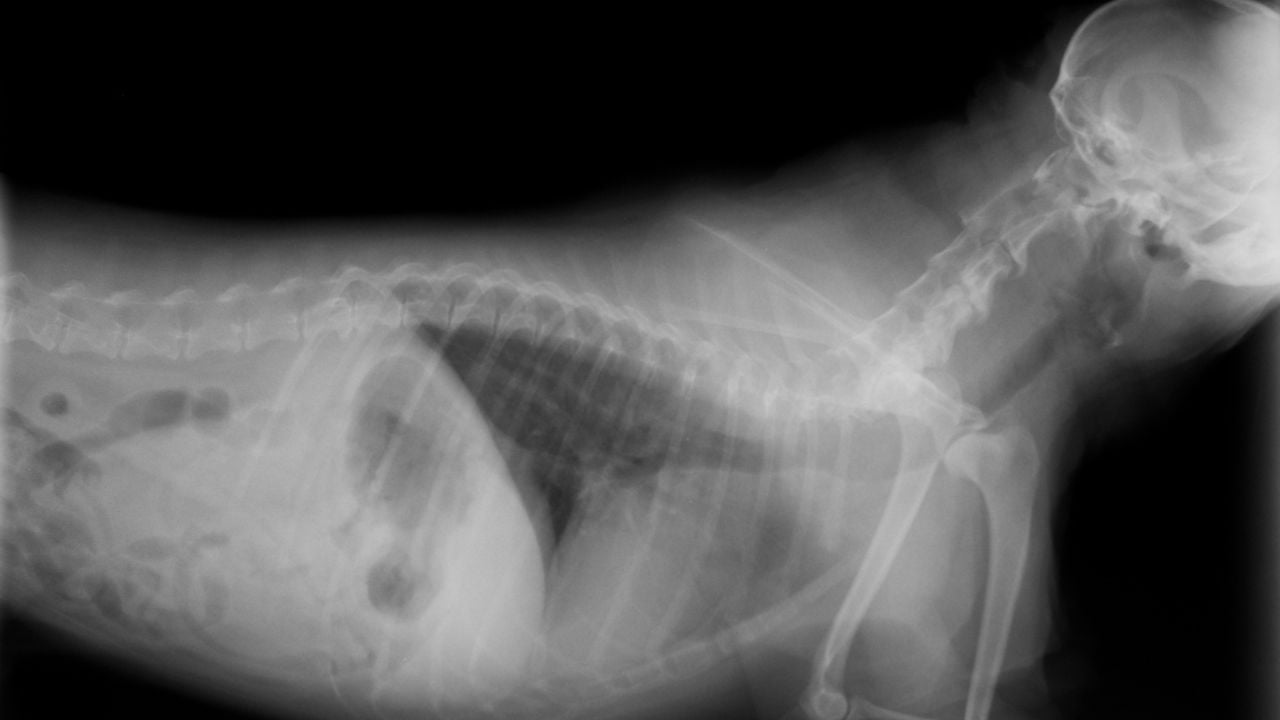

まず、犬には人間のような「鎖骨」がありません。

人間の場合、鎖骨は腕や肩を支える役割を果たしていますが、犬の場合はこの骨が退化しています。

そのため、犬の肩は筋肉や腱によって支えられており、非常に柔軟な構造になっています。このおかげで、犬は走ったり、ジャンプしたりといった多彩な動きができるように進化しています。